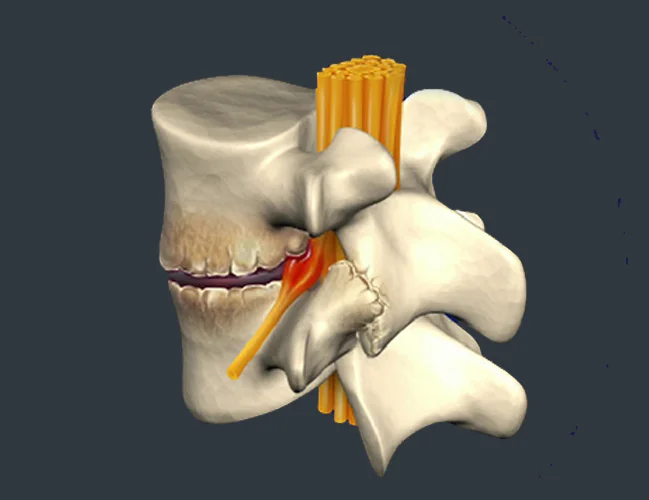

A herniated disc, also referred to as a slipped disc, ruptured disc, or disc herniation, is one of the most common causes of back pain. Often, people visit a spine specialist for back pain and unknowingly have a herniated disc. Herniated discs affect the vertebrae, the bones that make up your spine, and the spinal discs, which provide support and flexibility to your back.

Lumbar disc herniation happens when discs between vertebrae shift or rupture, compressing spinal nerves. Symptoms include lower back pain, leg weakness, and numbness.